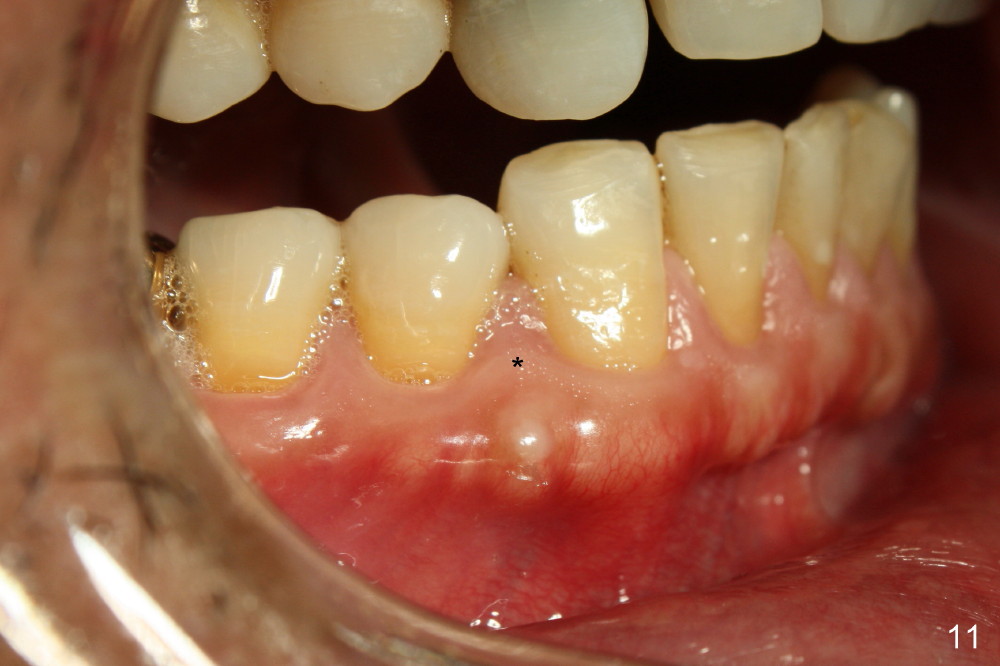

The tooth is discolored probably due to the side-effect of MTA(Fig.9; photo taken 9 months post-MTA).  The mesial gingiva recedes (*).  There is mild persistent pain with purulent discharge mesiobuccally (Fig.10 >).  The corresponding pocket remains 7-8 mm deep in spite of root canal therapy and MTA.

Treatment plan is to extrude #6 by placing a mini-implant between #27 and 28 (Fig.11-13) until the fracture line is exposed and the chronic infection is controlled.  The most importantly, the extrusion is expected to bring down the mesial papilla and the alveolar bone.  If the remaining root is not stable, the tooth is extracted and replaced by an implant.